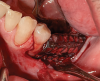

After 5.5 months, a new CBCT was made, which showed good-quality bone around the implant. Before mesh removal, a 500 mg 3 times a day 7-day amoxicillin regimen was given, starting 1 hour before surgery. After flap release (Figure 7), the mesh was removed and the implant was found to be covered crestally by solid bone, which was removed in order to place the healing abutment (Figure 8).

Fig 7. Mesh visible after flap release.

Figure 7